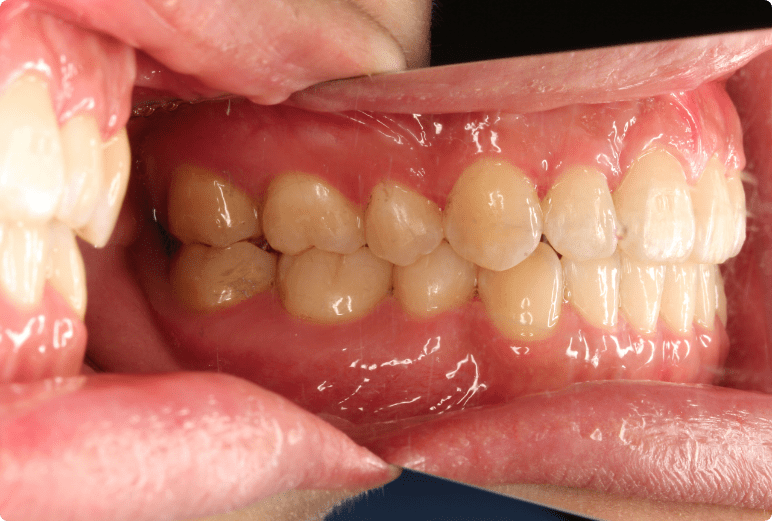

開咬を矯正治療で改善した症例

BEFORE

AFTER

症例概要

年代、性別

20代 女性

主訴

前歯で物が噛めない、でこぼこ

診断

骨格性Ⅲ級、歯性Ⅲ級、開咬、前歯部叢生

治療内容

非抜歯、唇側ワイヤー矯正、リテーナー

治療期間

約1.5年+メンテナンス

治療リスク

痛み、歯根吸収、歯肉退縮、ブラックトライアングル

治療費用

990,000円(税込)